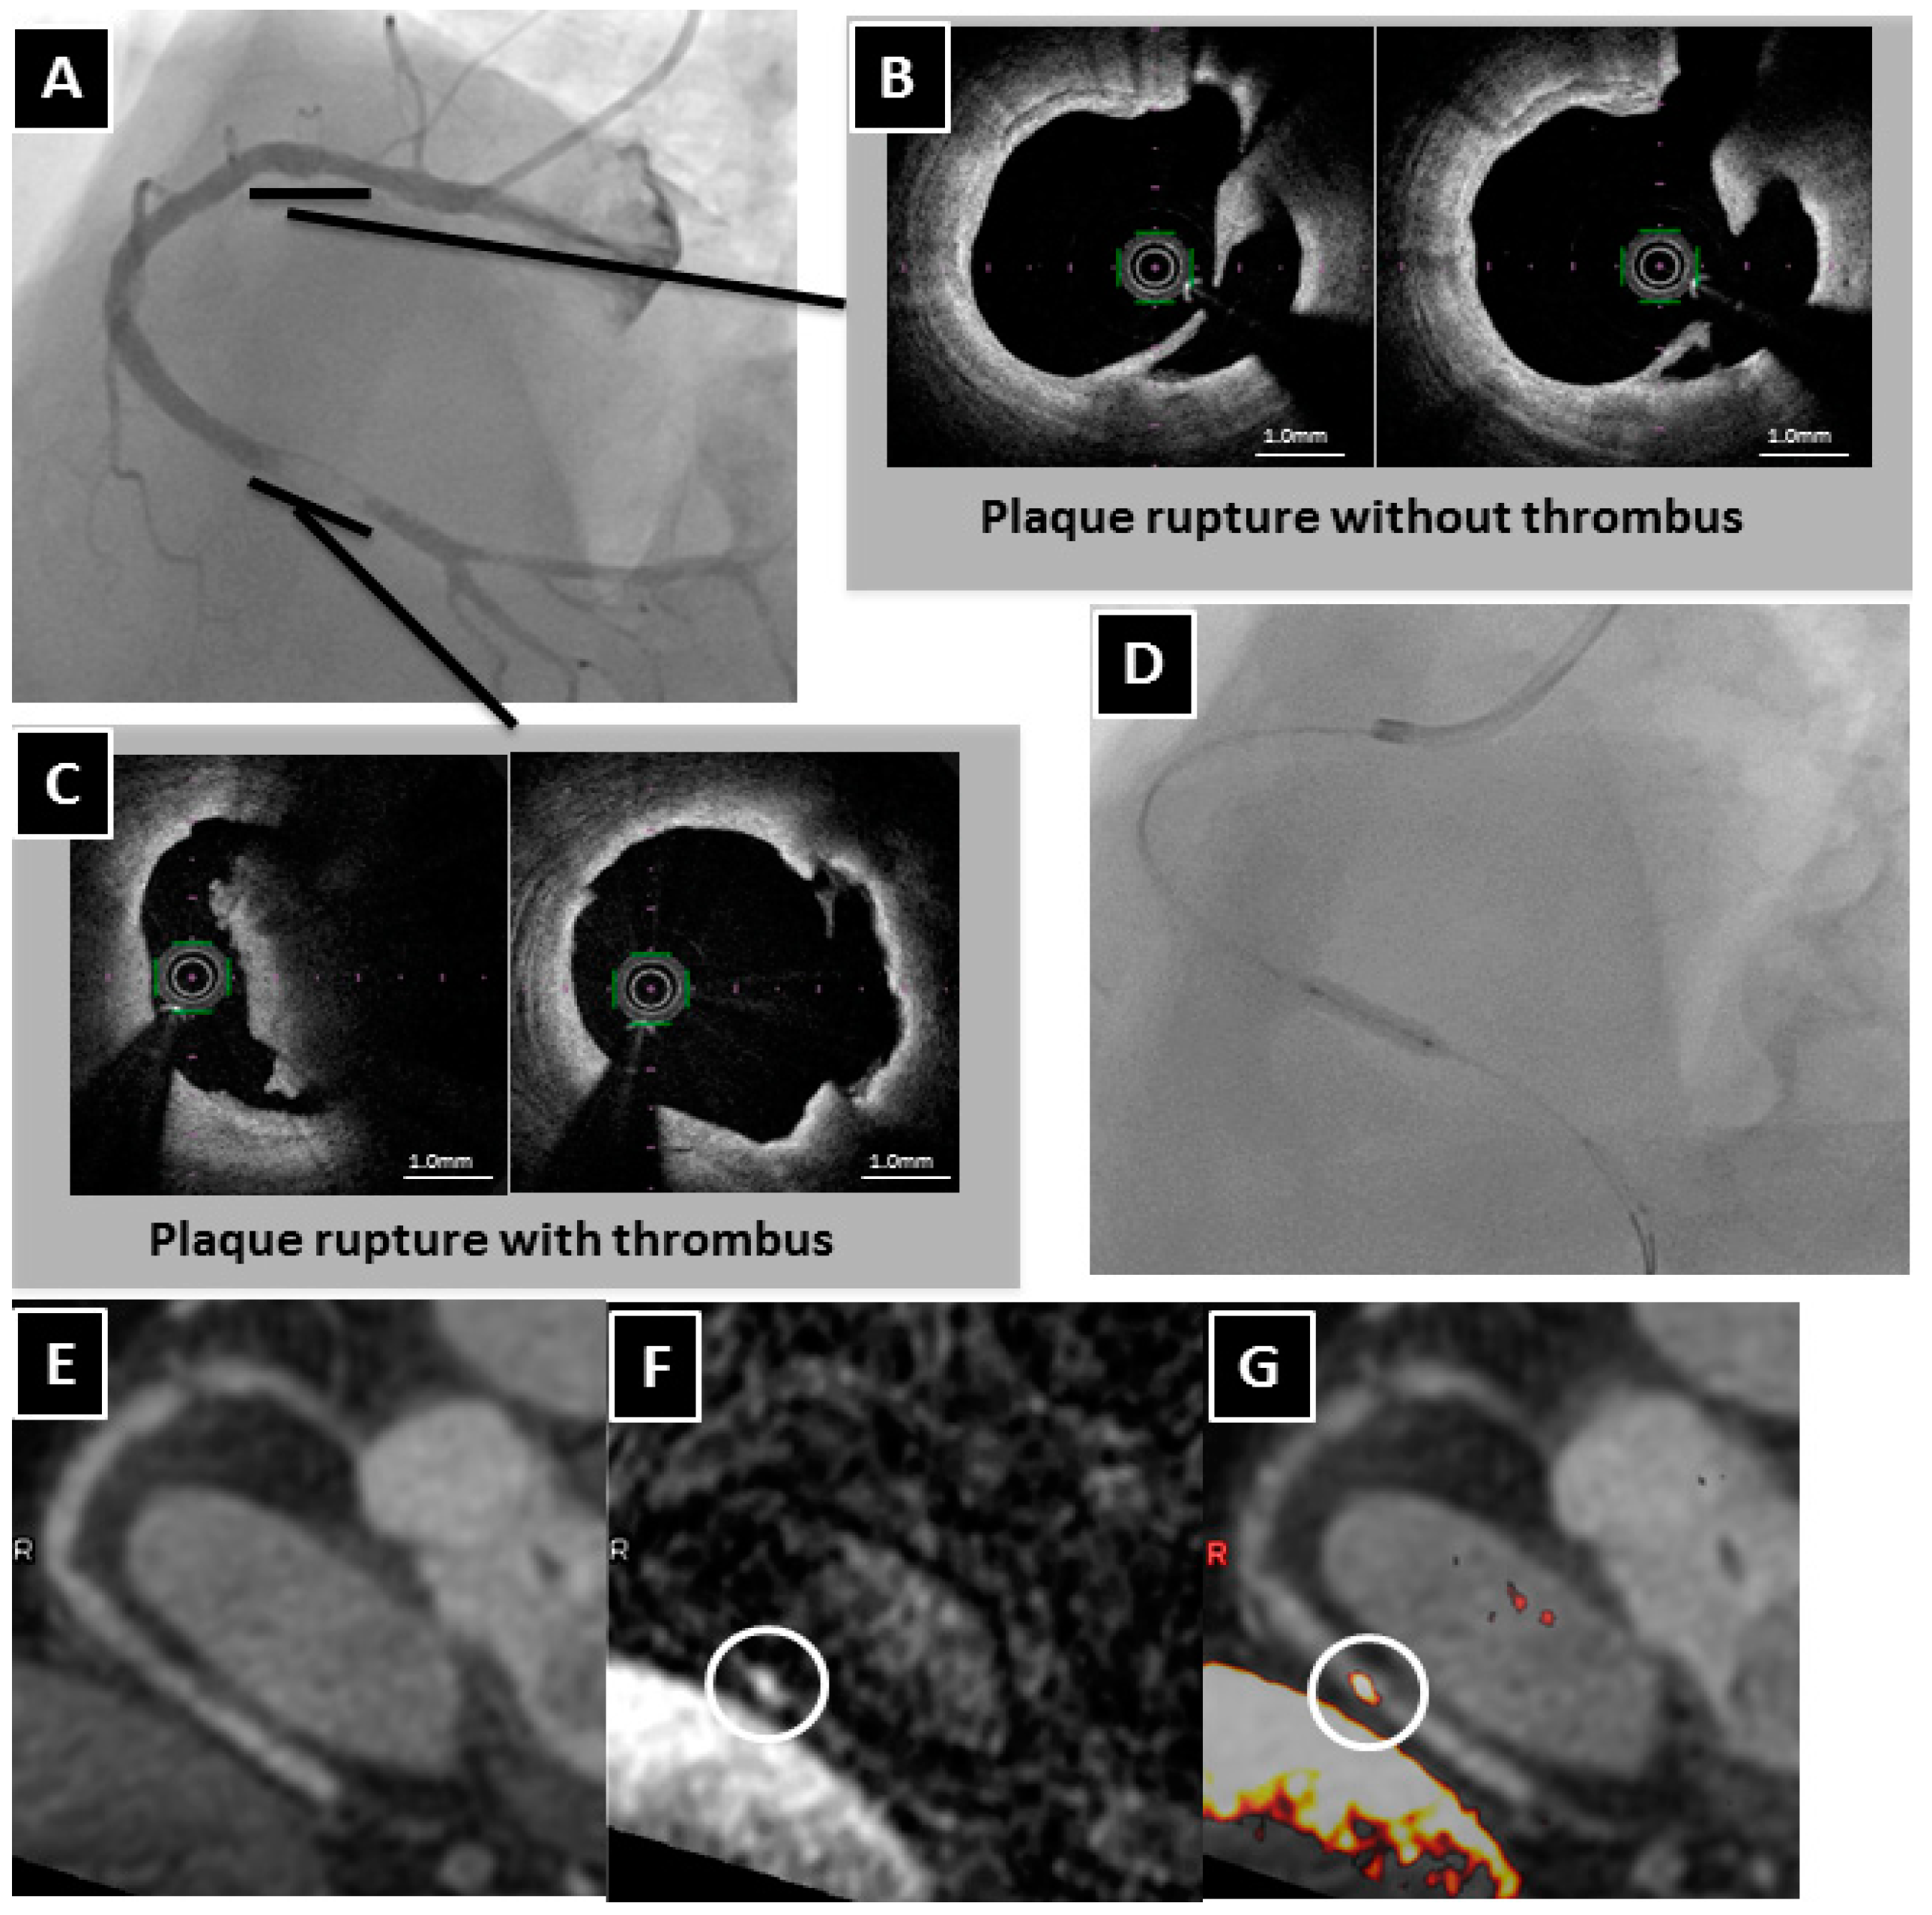

- Ehara, S.; Hasegawa, T.; Nakata, S.; Matsumoto, K.; Nishimura, S.; Iguchi, T.; Kataoka, T.; Yoshikawa, J.; Yoshiyama, M. Hyperintense plaque identified by magnetic resonance imaging relates to intracoronary thrombus as detected by optical coherence tomography in patients with angina pectoris. Eur. Heart J. 2012, 13, 394–399. [Google Scholar] [CrossRef] [PubMed]

- Matsumoto, K.; Ehara, S.; Hasegawa, T.; Sakaguchi, M.; Otsuka, K.; Yoshikawa, J.; Shimada, K. Localization of coronary high-intensity signals on T1-weighted MR imaging: Relation to plaque morphology and clinical severity of angina pectoris. J. Am. Coll. Cardiol. 2015, 8, 1143–1152. [Google Scholar] [CrossRef] [PubMed]

- Matsumoto, K.; Ehara, S.; Hasegawa, T.; Otsuka, K.; Yoshikawa, J.; Shimada, K. Prediction of the filter no-reflow phenomenon in patients with angina pectoris by using multimodality: Magnetic resonance imaging, optical coherence tomography, and serum biomarkers. J. Cardiol. 2016, 67, 430–436. [Google Scholar] [CrossRef] [PubMed]